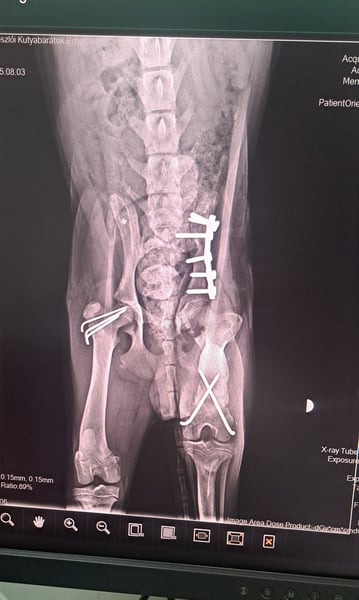

Der kleine Mango wurde von einem Auto angefahren und musste operiert werden.

Er hatte 3 Knochenbrüche, die mittlerweile gut verheilt sind.